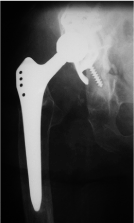

X-ray of the right hip showed a stable reconstruction of the acetabulum and the Wagner revision stem but dissociation of the head from the cone (Figure 5). We recommended revision of the hip but till today the patient is unwilling to undergo any revision surgery of the right hip. She is still using a wheel chair.

Figure 5. X - ray of the right hip (ap view) shows a stable reconstruction of the acetabulum and the Wagner revision stem but dissociation of the head from the cone with the head articulating with the cup.